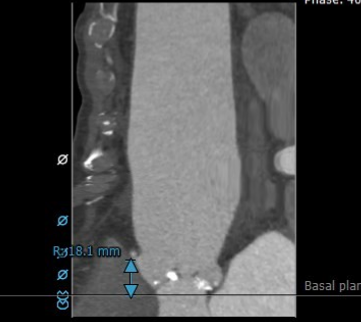

TAVR CT:STJ,升主动脉(瓣上40mm)

1.功能性二叶瓣,右无冠窦融合,重度钙化,左窦小,LCA开口高度9.4mm,极度横位心,心脏角度103°;

2.患者极度横位心,升主动脉及降主动脉3D扭曲,主动脉根部几呈鱼钩样,极大增加输送系统推送及瓣膜释放难度;